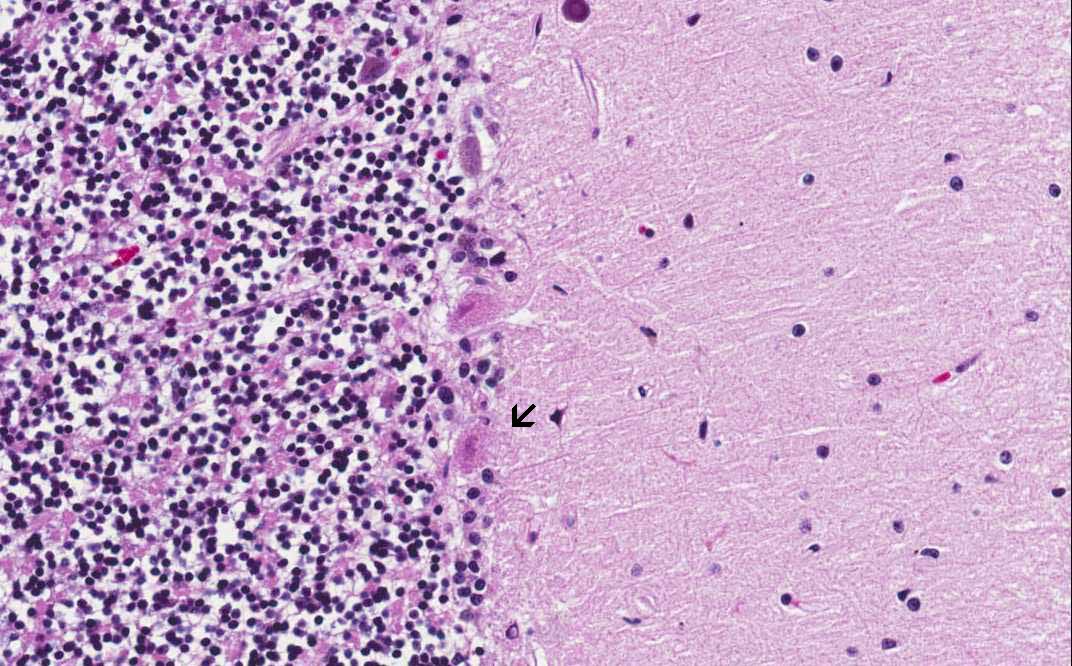

Area 2: At the periphery of the infarct, there is both viable internal granular cells (arrow) with the nuclei well stained by hematoxylin. Foamy histiocytes are noted in the white matter (W). Details of the foamy histiocytes (H) are shown on the panel on the right. Note the viable internal granular cells (IGC).